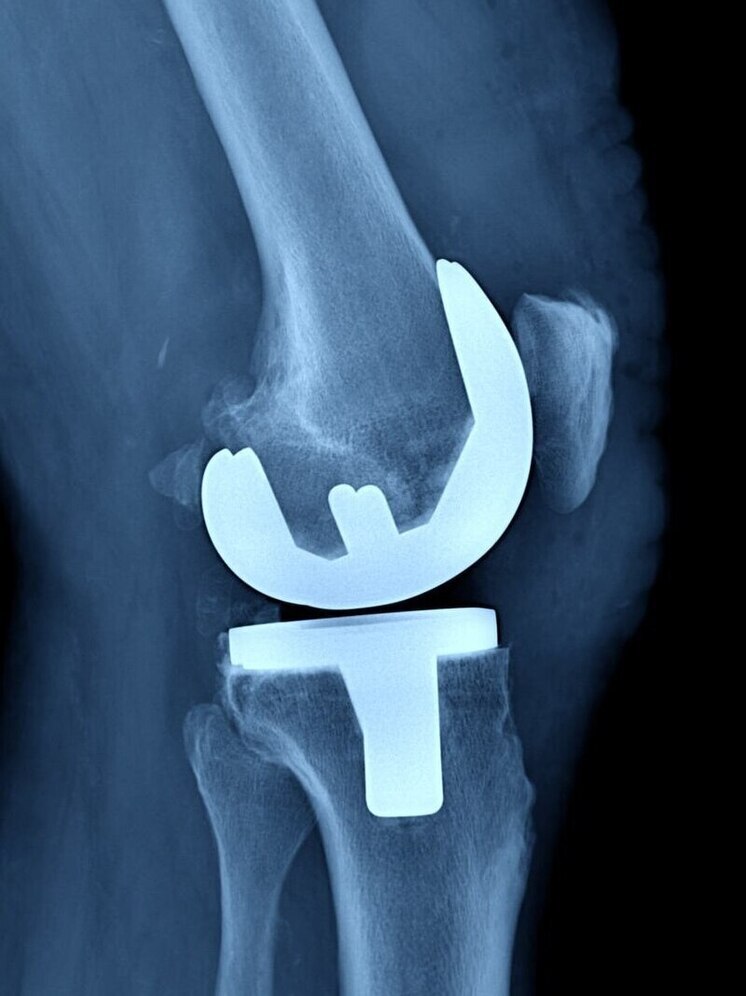

В Балахнинской центральной районной больнице начали проводить операции по эндопротезированию коленного сустава. уже успешно проведены пять таких процедур.

Как правило, развитие артроза обусловлено избыточной массой тела, перенесенными вирусными заболеваниями, повышенными физическими нагрузками, а также генетической предрасположенностью. После эндопротезирования сустава пациенты избавляются от болевого синдрома, восстанавливается амплитуда движений и возможность полноценной опоры на конечность.

Срок пребывания в стационаре после операции не превышает семи дней, а период восстановления после замены сустава составляет примерно 3-4 месяца.

Оперативное вмешательство осуществляется на бесплатной основе, в рамках программы обязательного медицинского страхования, сообщил представитель сферы здравоохранения региона Алексей Никонов в своём телеграм-канале.